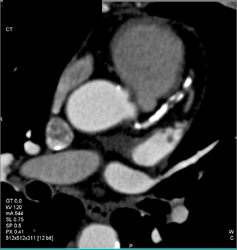

Diseased RCA